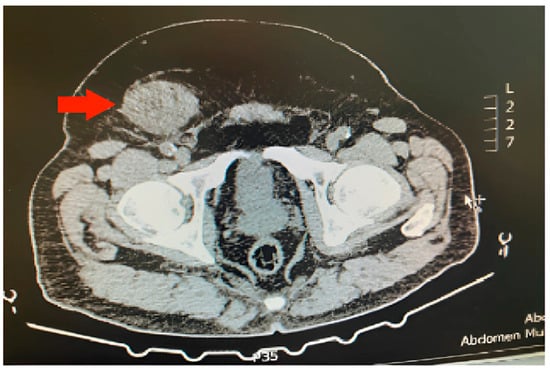

2. Case Report